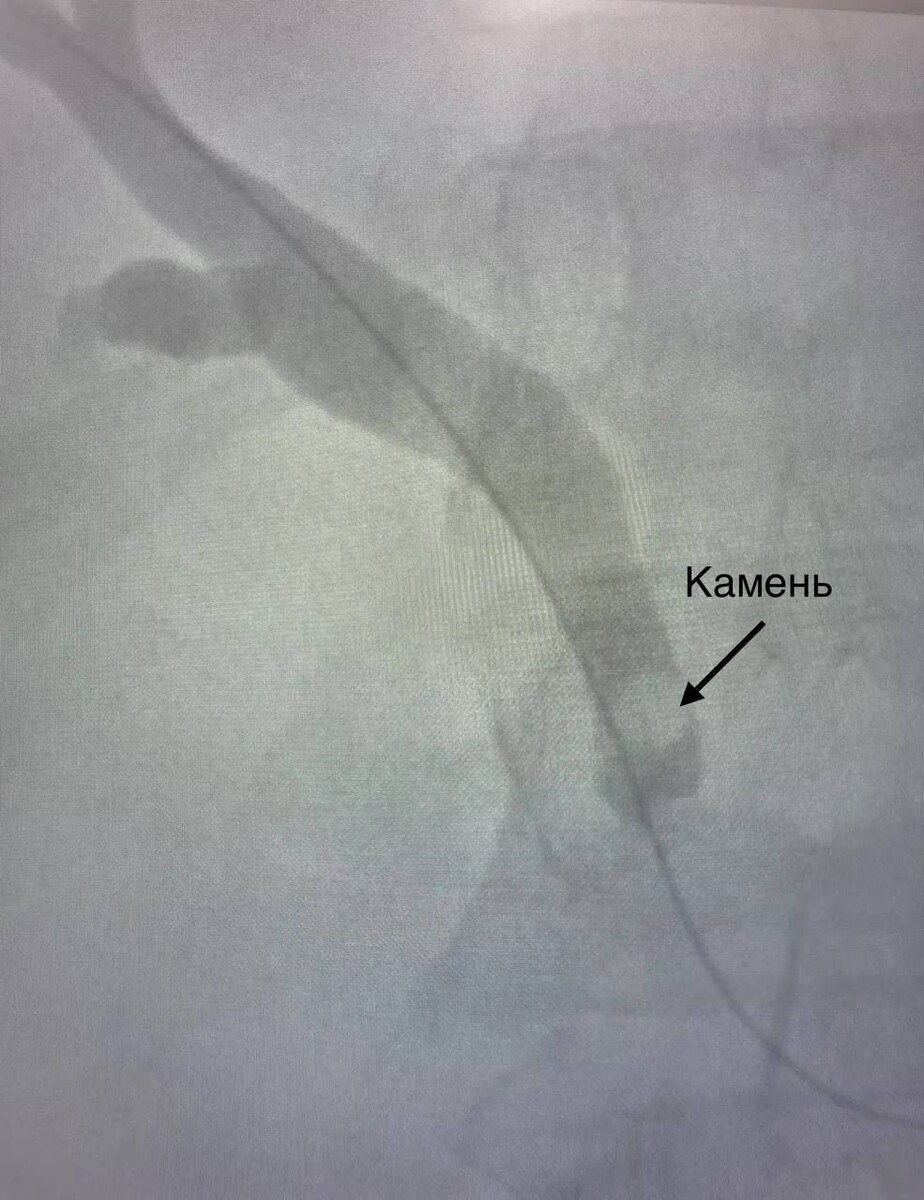

Камень, застрявший в желчном протоке челнинца, достали через маленький разрез

Под контролем рентгена хирурги провели мини-инвазивную операцию. Через маленький разрез пациенту ввели проводник, через который хирурги с помощью инструментов выполнили удаление камня.

«Через протоки печени мы ввели специальный инструмент в виде петли, захватили камень и достали его, используя жесткий тубус. Действовать нужно было аккуратно, просчитывая каждый миллиметр, в этом и была сложность. Подобную операцию мы проводили впервые, все прошло успешно. Пациент все время был в сознании, под местной анестезией» - говорит рентгенхирург Зоя Антропова.